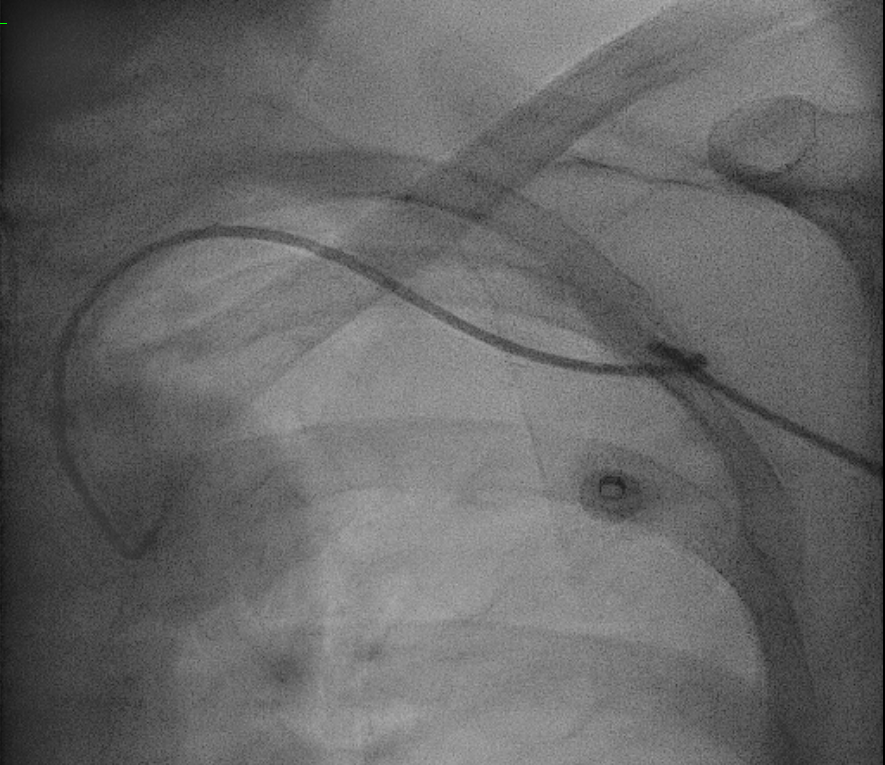

While attempting to engage right coronary artery, noted loss of pressure.

Catheter kinked in a figure of 8 position around left subclavian area.

Attempted to unkink by untwisting with 0.035" J tip guidewire support of failed.

Kinked part of catheter brought down to left arm area and attempted to unkink with inflated cuff and compression was not successful as well.

Right femoral puncture and Snare Amplatz Goose Neck 20mm advanced to distal tip of catheter.

Distal tip of catheter was snared and manage to unkink catheter.

Optitorque 5FR catheter successfully removed from left radial sheath.